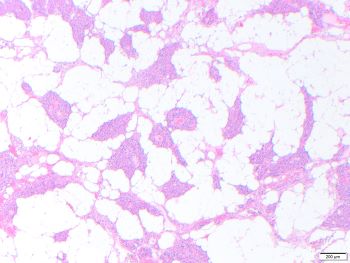

Parathyroid lipoadenoma

Parathyroid lipoadenoma is a rare cause of hyperparathyroidism. Lipoadenomas show significant increase in both adipose tissue and parenchymal tissue, occasionally resembling normal proportions in histologic assessment. There is marked enlargement of the gland, in this case 2.2 g. Histologically, when more than 50% of the volume of the enlarged gland is adipose tissue, the diagnosis of lipoadenoma is warranted over adenoma.

The normal weight of each parathyroid gland is 30-40 mg, and greater than 80 mg is considered abnormal. Each gland is composed of fat cells, Oxyphil cells and Chief cells. Normocellular parathyroid glands have highly variable amounts of adipose tissue. In adults normal parathyroid may have approximately 50% adipose tissue, but may have as little as 10%. Hyperplasia usually involves all four glands, with similar histology to adenoma.